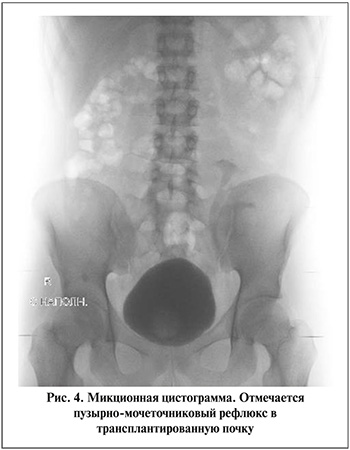

По данным ранее проведенных исследований доказана важная роль инфравезикальной обструкции и дисфункции мочевого пузыря по типу гипертонии или гиперактивного мочевого пузыря (ГАМП) в развитии пузырно-мочеточникового рефлюкса в трансплантированную почку [24] (рис. 4). Инфравезикальная обструкция была исключена у всех пациентов. Диагностированный ПМР отмечен у 10 пациентов, всем было проведено комплексное уродинамическое исследование. Признаки ГАМП выявлены у семи пациентов, четырем на фоне консервативной терапии М-холинолитиками отмечен положительный эффект и в последующем обострений пиелонефрита отмечено не было. Тем не менее в шести случаях потребовалась коррекция в связи с прогрессирующей дисфункцией трансплантированной почки и сохраняющимися обострениями пиелонефрита, при этом всем пациентам с ГАМП продолжена терапия М-холинолитиками. Четырем пациентам из шести при трансплантации был выполнен прямой уретероцистоанастомоз, двум – с антирефлюксным компонентом в модификации по Лич Грегуару.